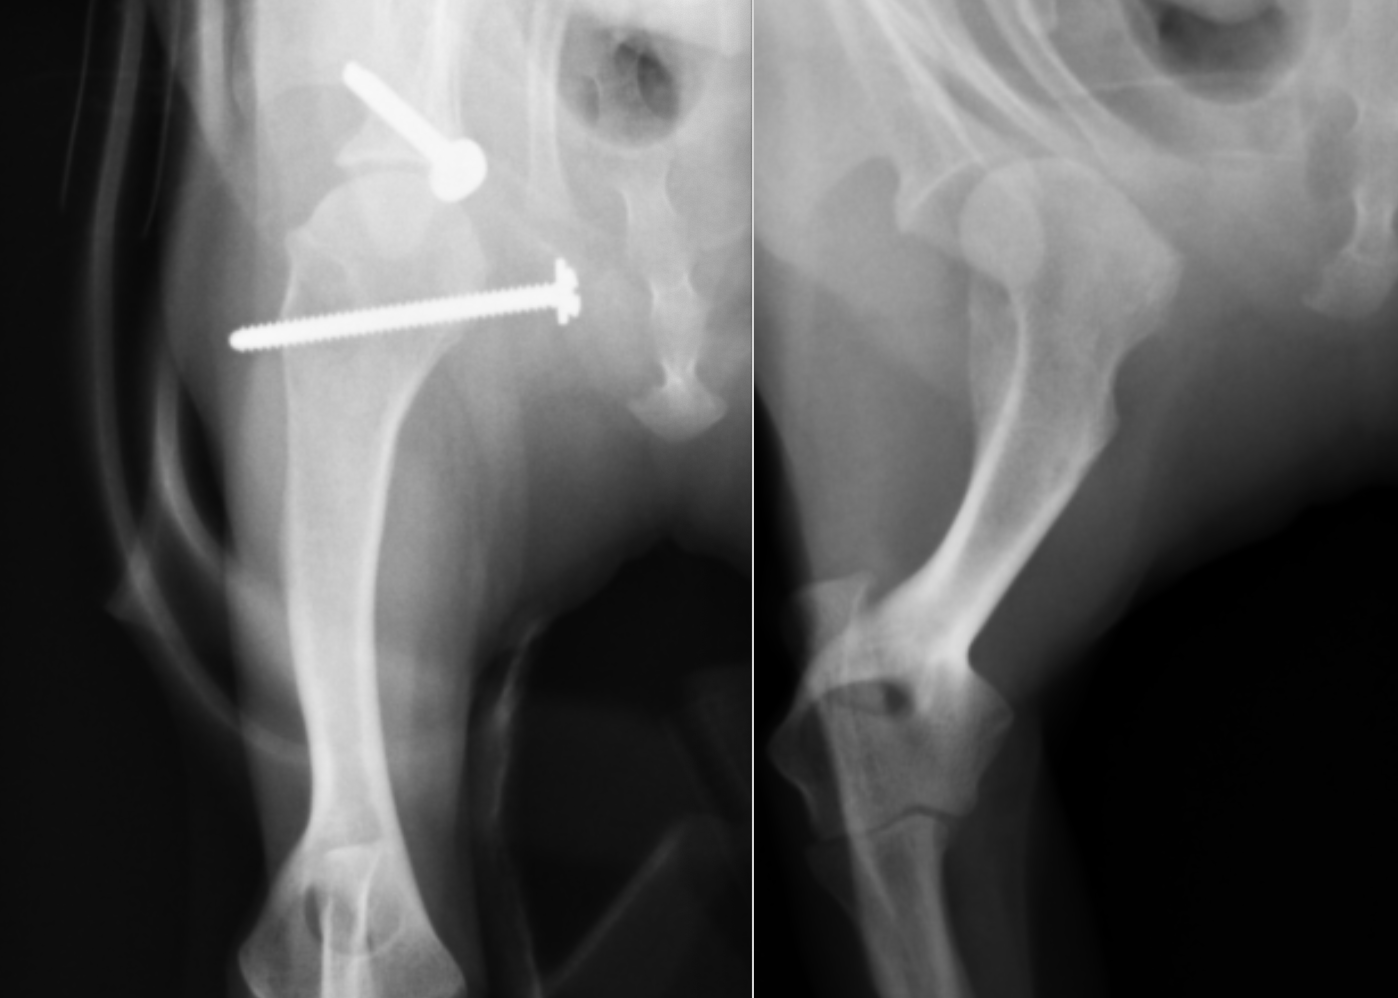

横から見たレントゲンです。右が術前、左が術後です。こちらも線を引くと

右のレントゲンではオレンジと赤のラインが全く合っていなかったのが、左の術後ではピッタリとあっているのがわかると思います。